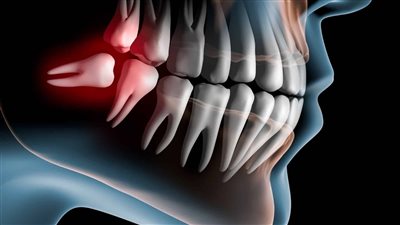

كشف الدكتور محمد أبو السعود، أخصائي زراعة الأسنان عملية خلع ضرس العقل المدفون بنج كامل، مشيرا إلى أن الطبيب يجري ثقوبا صغيرة في اللثة، مع إزالة جزء من العظام المحيط بالسن، بهدف الوصول إلى ضرس العقل المدفون.

وأضاف أخصائي زراعة الأسنان، أن عملية خلع ضرس العقل المدفون بنج كامل، تستغرق وقتا يصل إلى ساعة أو أكثر، حيث يجري الطبيب بعد الانتهاء من خلع الضرس خياطة لمكان الجرح، مشيرا إلى أن هناك حالات تستدعي خلع ضرس العقل جراحيا، وهي تكون كالآتي:

- إذا كان الشخص يعاني من جذور شديدة الانحناء لضروس العقل.

- وأيضا إذا كان ضرس العقل مكسورا بدرجة كبيرة.

- وأخيرا إذا كان الضرس مدفونا.